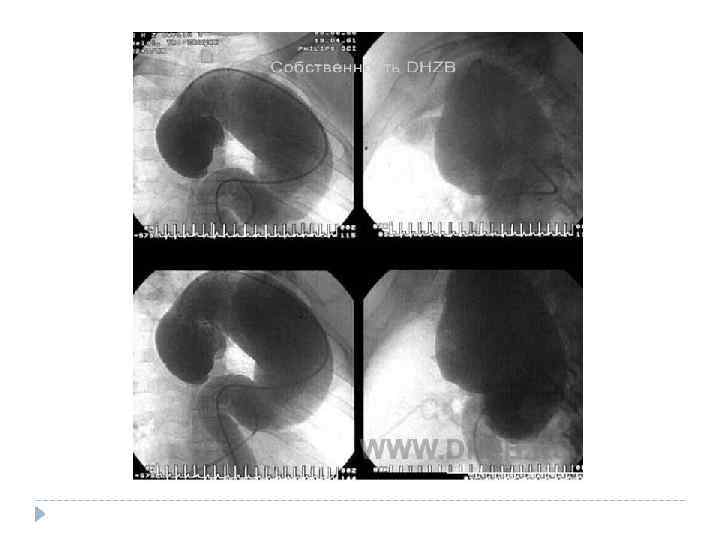

Расслаивающая аневризма аорты — разрыв аорты, который приводит к тому, что кровь затекает между слоями стенок аорты и расслаивает их дальше. Если расслоение прорывает стенку аорты полностью (все три слоя), то происходит быстрая массивная кровопотеря. В более чем 90% случаев это приводит к смерти, даже если вовремя начато правильное лечение. при надрыве интимы — боль и коллаптоидные реакции; при расслоении стенки аорты — резкая мигрирующая боль, анемизация, органные симптомы, повторные коллаптоидные реакции; при полном разрыве стенки сосуда — признаки внутреннего кровотечения и терминальный геморрагический шок.

Расслаивающая аневризма аорты — разрыв аорты, который приводит к тому, что кровь затекает между слоями стенок аорты и расслаивает их дальше. Если расслоение прорывает стенку аорты полностью (все три слоя), то происходит быстрая массивная кровопотеря. В более чем 90% случаев это приводит к смерти, даже если вовремя начато правильное лечение. при надрыве интимы — боль и коллаптоидные реакции; при расслоении стенки аорты — резкая мигрирующая боль, анемизация, органные симптомы, повторные коллаптоидные реакции; при полном разрыве стенки сосуда — признаки внутреннего кровотечения и терминальный геморрагический шок.

Систолический шум Почти у половины больных с рассливающей аневризмой аорты отмечаются признаки аортальной недостаточности - диастолический шум и снижение уровня диастолического артериального давления. Исключение ишемии по ЭКГ RG, КТ, тотальная аортография

Систолический шум Почти у половины больных с рассливающей аневризмой аорты отмечаются признаки аортальной недостаточности - диастолический шум и снижение уровня диастолического артериального давления. Исключение ишемии по ЭКГ RG, КТ, тотальная аортография